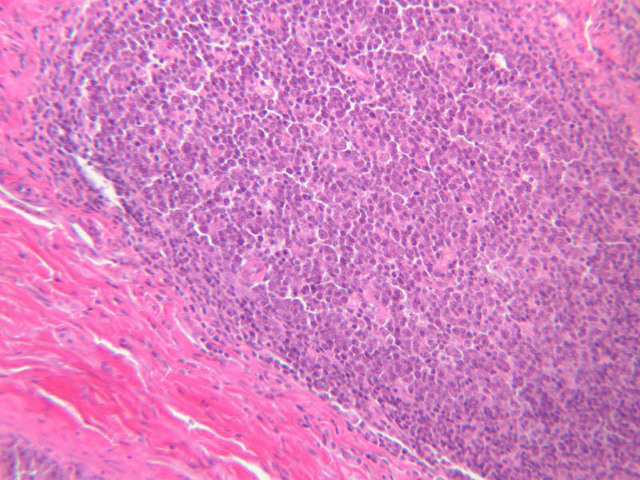

Blood passes from the elastic arteries via arteries of intermediate type into the muscular (distribution) arteries. Locate and examine a muscular artery in slide A-28 (Renal artery & vein, H&E [2.5x, 10x-labeled, 20x, 40x-labeled] [10x-labeled, 20x, 40x]; AF [10x-labeled, 20x, 40x]). Note that the tunica intima is separated from the tunica media by a thick internal elastic membrane which has a scalloped appearance. The tunica media consists of many layers of smooth muscle cells arranged concentrically in a spiral fashion (A-28, H&E [2.5x, 10x-labeled, 20x, 40x] [2.5x, 10x, 20x, 40x, 40x] [2.5x, 10x, 20x]). An external elastic membrane is present, but is thinner and less complete than the internal elastic membrane. The tunica adventitia is about equal in size to the media in this vessel and is more intensely eosinophilic in its staining properties. Note the appearance of small blood vessels in the outer part of the tunica adventitia. You may also be able to see occasional nerve fibers.